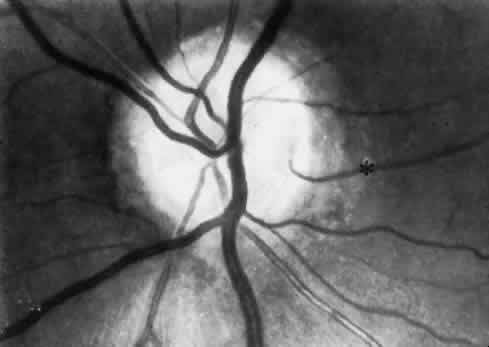

In as many as 20% of normal eyes, a cilioretinal artery may exist as well.11 These are vessels that directly connect the posterior ciliary circulation to the retinal circulation. Clinically, they can usually be identified by their ophthalmoscopic appearance. Cilioretinal vessels emerge from the edge of the optic disc, with no apparent connection to the central retinal vessels (Fig. 2). Fluorescein angiography shows them to fill with the choroidal circulation. They are usually temporally located on the optic disc but rarely can be nasal. Multiple vessels may be present. Cilioretinal arteries are the easiest to identify. The existence of cilioretinal venous channels in normal eyes is a subject of debate.12 Acquired cilioretinal veins, referred to as optociliary anastomoses or incorrectly as optociliary shunts, can develop in pathologic processes such as obstruction of the CRV or in optic nerve tumors (Fig. 3).

Fig. 2. The cilioretinal artery hooks around the temporal margin of the disc edge (*). (Henkind P, Benjamin JV: Trans Ophthalmol Soc UK 96:418, 1976)